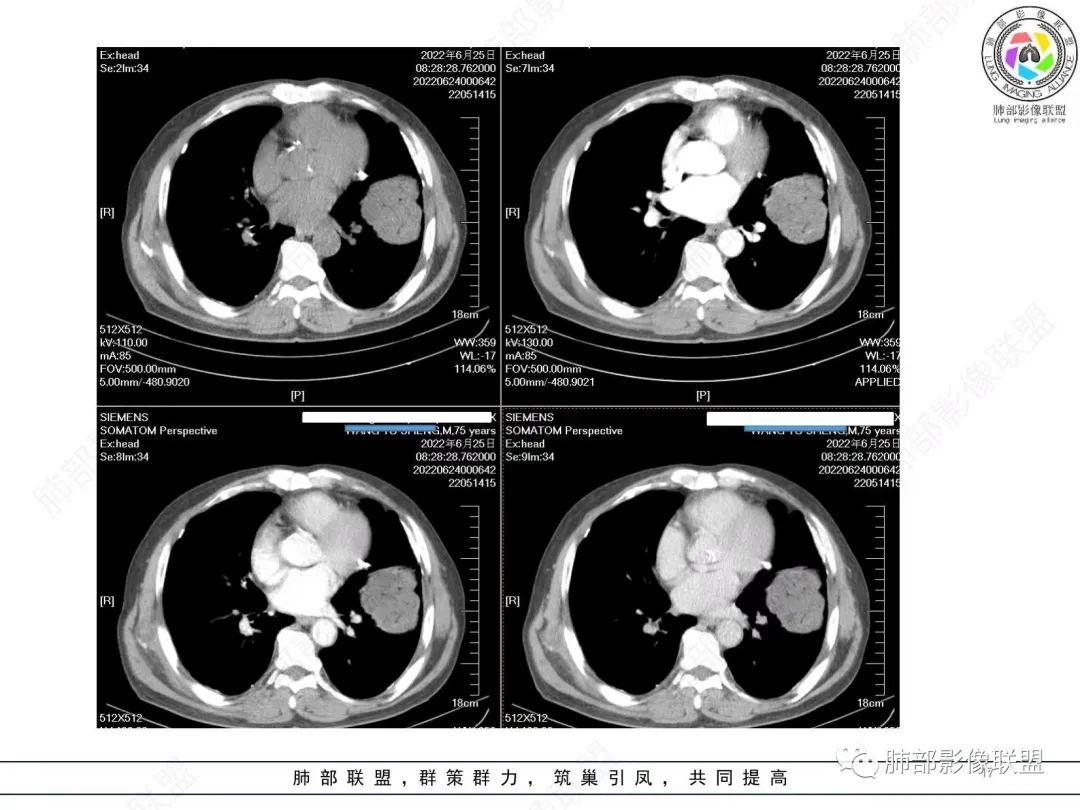

4)密度:肿块平扫为软组织密度,由于体积较大,内部常见大片状坏死,可出现不规则厚壁空洞或坏死内多发无壁小空洞,坏死多不均匀:坏死灶内可见如柳絮样的斑片样强化灶,坏死边缘与非坏死区分界不清本例坏死较明显,密度不均匀。

5)肿瘤强化方式:肺部恶性肿瘤强化程度与其血供丰富程度相关,血供丰富多强化明显,反之则较差。由于PSC 周边实性部分富血供及内部黏液变性、坏死,增强后肿块多数呈轻-中度边缘环形强化或不均匀小斑片状强化。国外学者对照病理发现肿瘤细胞或胶原组织增强扫描时强化,无强化的低密度区代表了黏液样变性区和出血坏死区。

(赖晓宇老师总结)